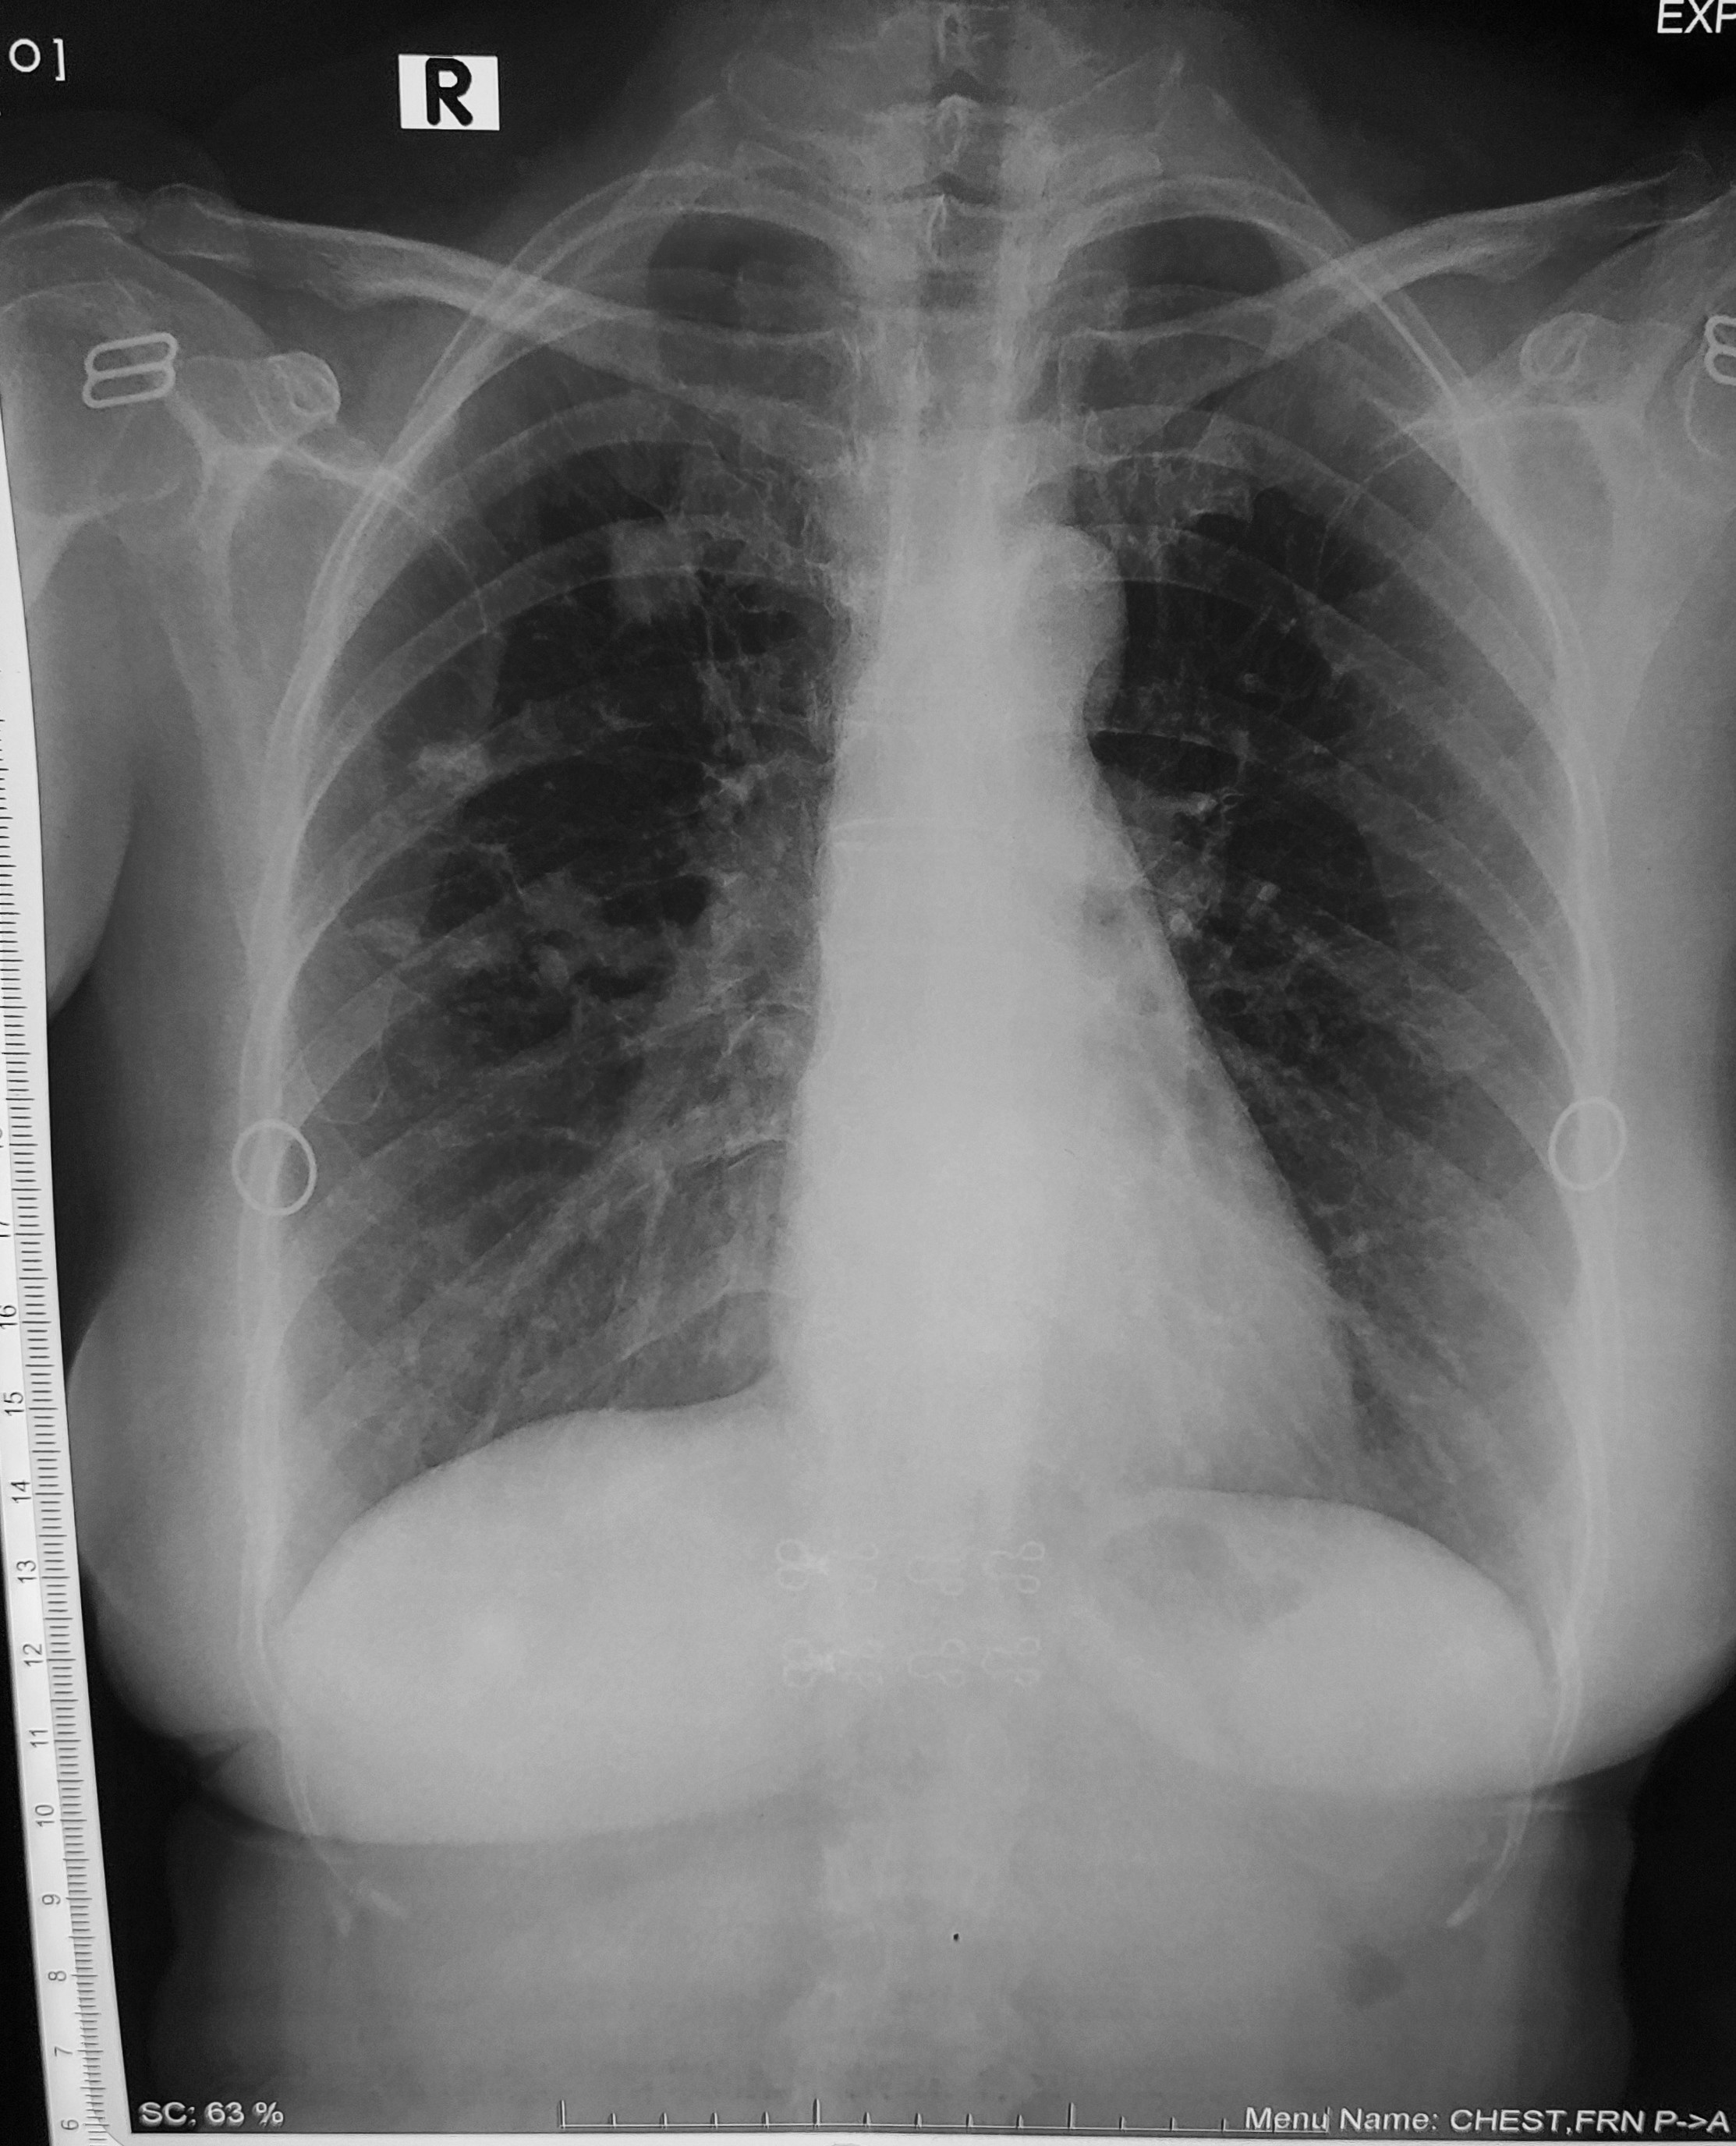

Bệnh nhân nữ 22 tuổi. Đau ngực khi thở trong vài ngày nay và khó thở. Đến phòng cấp cứu do các triệu chứng này, với CRP tăng nhẹ 44, D-dimer 5.2 µg/mL (bình thường <0.5 µg/mL), TnT bình thường, CTM bình thường. Không ghi nhận triệu chứng khác. Thỉnh thoảng hút thuốc, uống bia chủ yếu với bạn bè vào cuối tuần, không quá nhiều. Không có tiền sử bệnh mãn tính. Đang dùng thuốc tránh thai. HA 110/80, M 100.